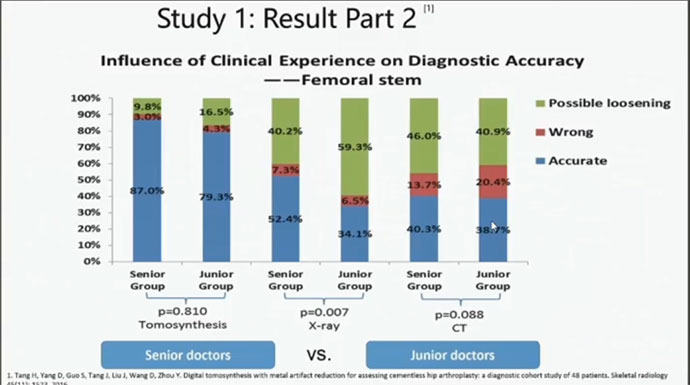

视金识功能可以大大的提高诊断的一致性。减少诊断误差的同时,减少了经验对诊断结果的影响。 视金识的诊断精度在不同经验的医生中可以达到87%及79%的极高精确度。误差更是缩减到3%及4.3%。